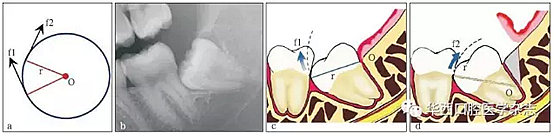

3.3.1 轉(zhuǎn)動(dòng)軸心與圓弧運(yùn)動(dòng) 這一原理在前傾或水平阻生智齒的拔除中運(yùn)用最廣??梢酝ㄟ^改變牙體轉(zhuǎn)動(dòng)脫位時(shí)的運(yùn)動(dòng)軸心,來改變牙體上各點(diǎn)的運(yùn)動(dòng)方向(圖 4),從而避開阻力而使牙齒脫位。但在此過程中,牙槽窩的擠壓變形仍不可避免。尤其是舌側(cè)骨板的骨折,更是經(jīng)常發(fā)生的事件。要進(jìn)一步減少對(duì)牙槽窩的擠壓,則需要對(duì)牙根進(jìn)行進(jìn)一步的切割。

在圓周運(yùn)動(dòng)(旋轉(zhuǎn))中,圓周上所有點(diǎn)的運(yùn)動(dòng)方向(f1、f2)均為切線方向,與通過該點(diǎn)的半徑(r)相垂直(圖a)。當(dāng)牙齒發(fā)生旋轉(zhuǎn)脫位時(shí),其阻力點(diǎn)的運(yùn)動(dòng)方向會(huì)隨著轉(zhuǎn)動(dòng)的軸心點(diǎn)的變化而變化,從而避開阻力。前傾阻生智齒(圖b)脫位時(shí),阻力分析如圖 c所示,因阻力點(diǎn)位于旋轉(zhuǎn)中心(O)的下方,旋轉(zhuǎn)脫位時(shí),其阻力點(diǎn)的運(yùn)動(dòng)方向(f1)是向前上的,被鄰牙所阻擋。如果按照?qǐng)D d所示,去除遠(yuǎn)中骨質(zhì)(灰色部分)或切割牙體(r)后,旋轉(zhuǎn)中心(O)下移,阻力點(diǎn)的運(yùn)動(dòng)方向就改變?yōu)橄蚝笊希╢2),而得以避開鄰牙阻擋而脫位。

圖4 轉(zhuǎn)動(dòng)軸心與圓弧運(yùn)動(dòng)